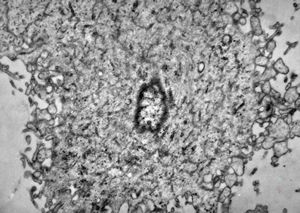

M,60y. | fibrinous pneumonia